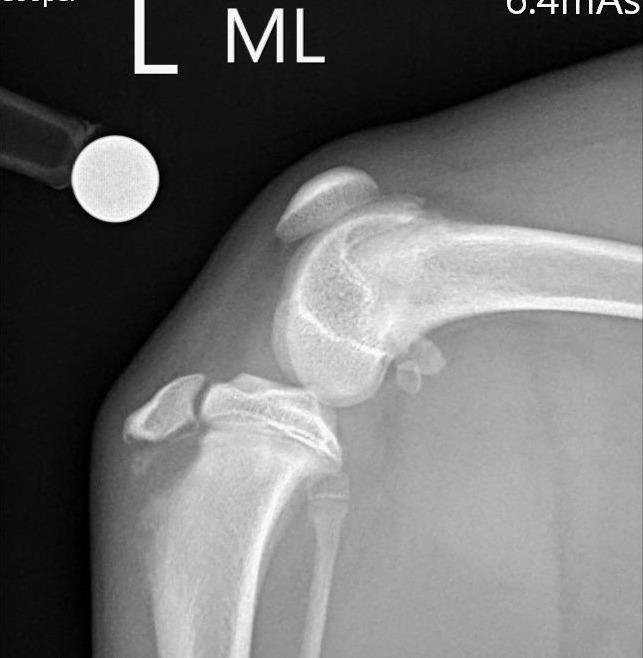

我們練習一下: 第一張照片R是正常的膝蓋, 找找看標記L的第二張 部分哪裡飛起來了呢?